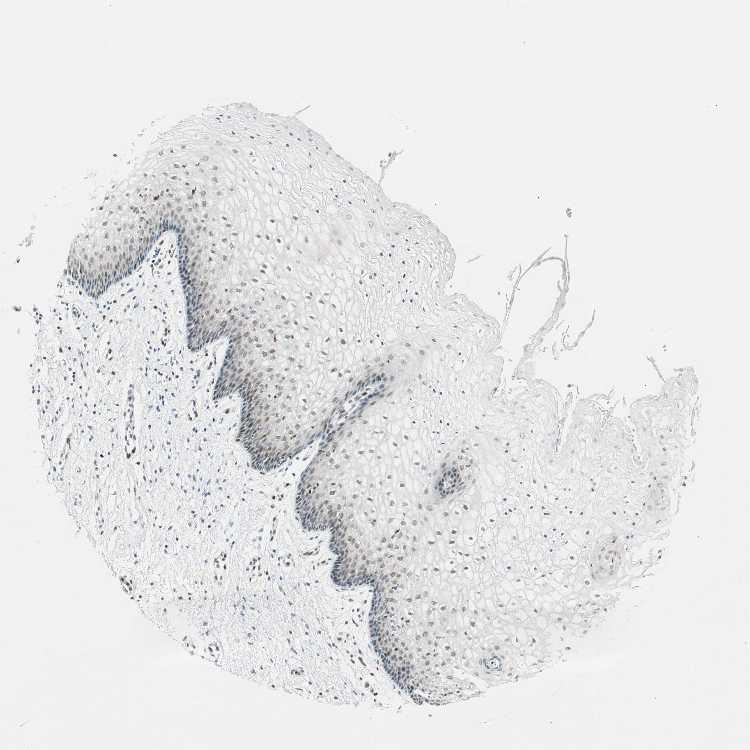

VAGINA - Antibody stainingi

Antibody staining in the annotated cell types in the current human tissue is reported as not detected, low, medium, or high, based on conventional immunohistochemistry profiling in selected tissues. This score is based on the combination of the staining intensity and fraction of stained cells.

Each image is clickable and will lead to virtual microscopy that enables deeper exploration of all samples and also displays staining intensity scores, fraction scores and subcellular localization as well as patient and tissue information for each sample.

Antibody HPA005652

Squamous epithelial cells Not detected